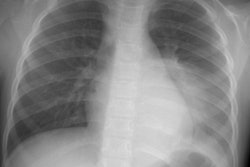

X-ray:

The lesion typically presents with a pleural effusion with associated smooth, nodular pleural thickening (resembling a mesothelioma).